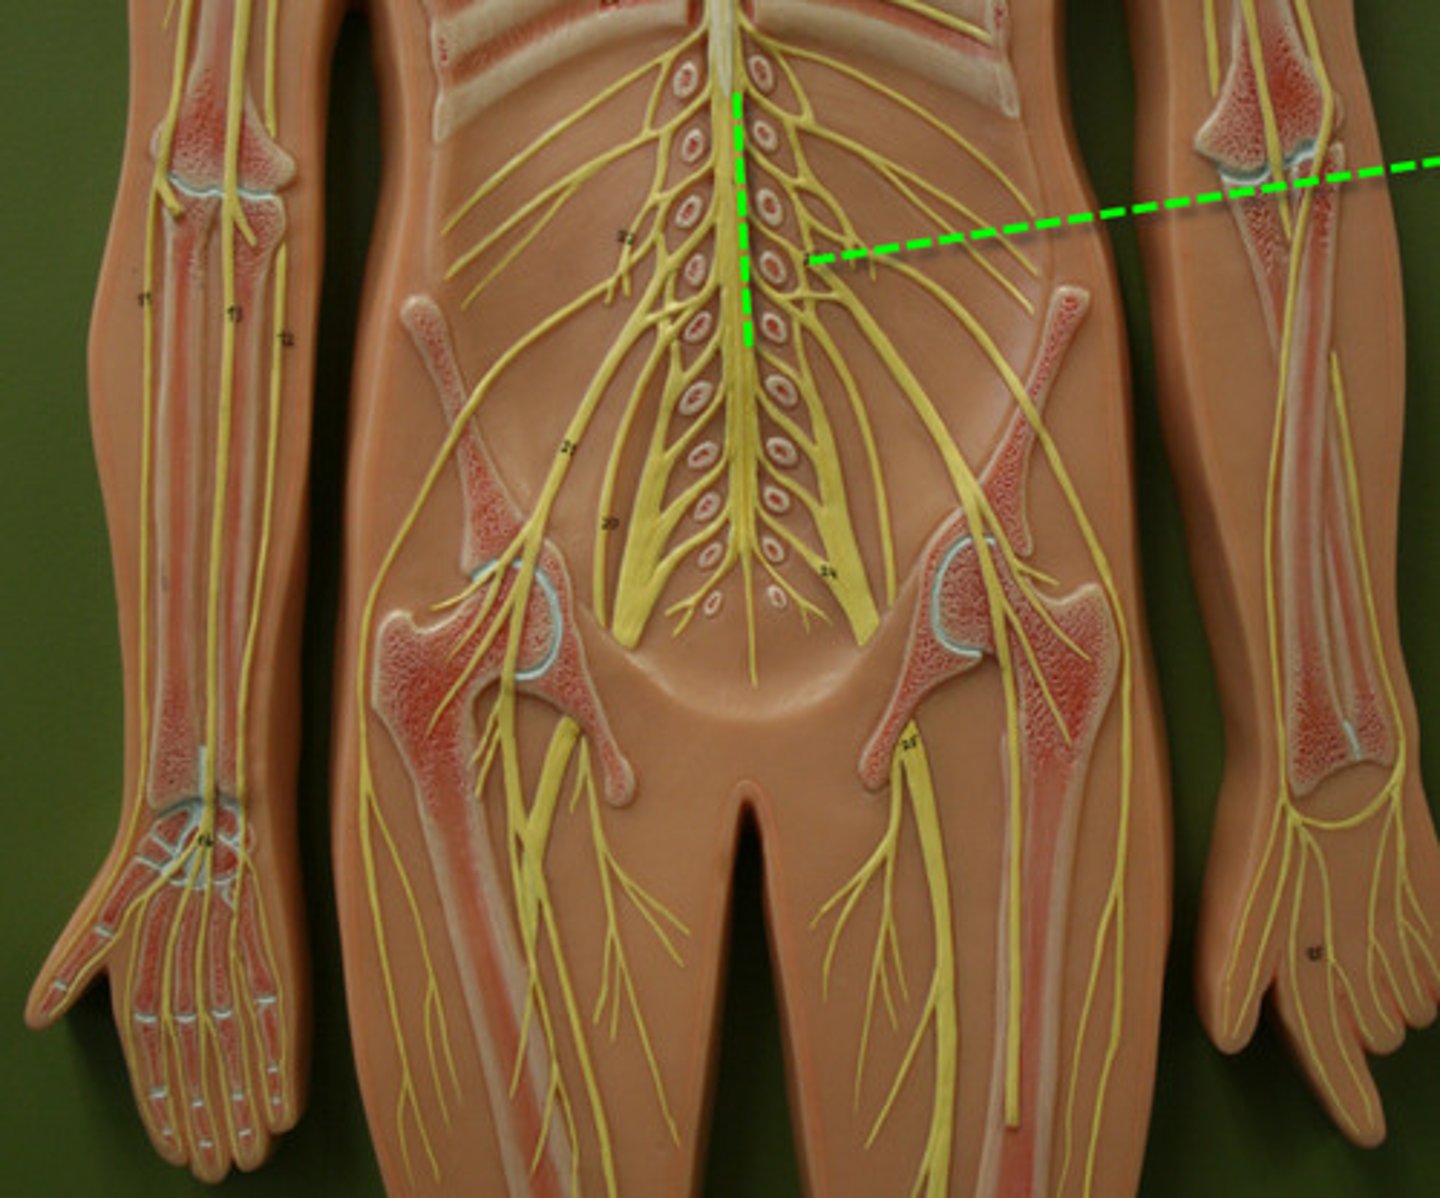

cervical plexus

C1-C5

brachial plexus

C5-T1

lumbar plexus

T12- L4

sacral plexus

L4- S4

genitofemoral nerve

Wishbone of the leg

lateral femoral cutaneous nerve

femoral nerve

saphenous nerve

posterior femoral cutaneous nerve

sciatic nerve

obturator nerve

common fibular nerve

tibial nerve